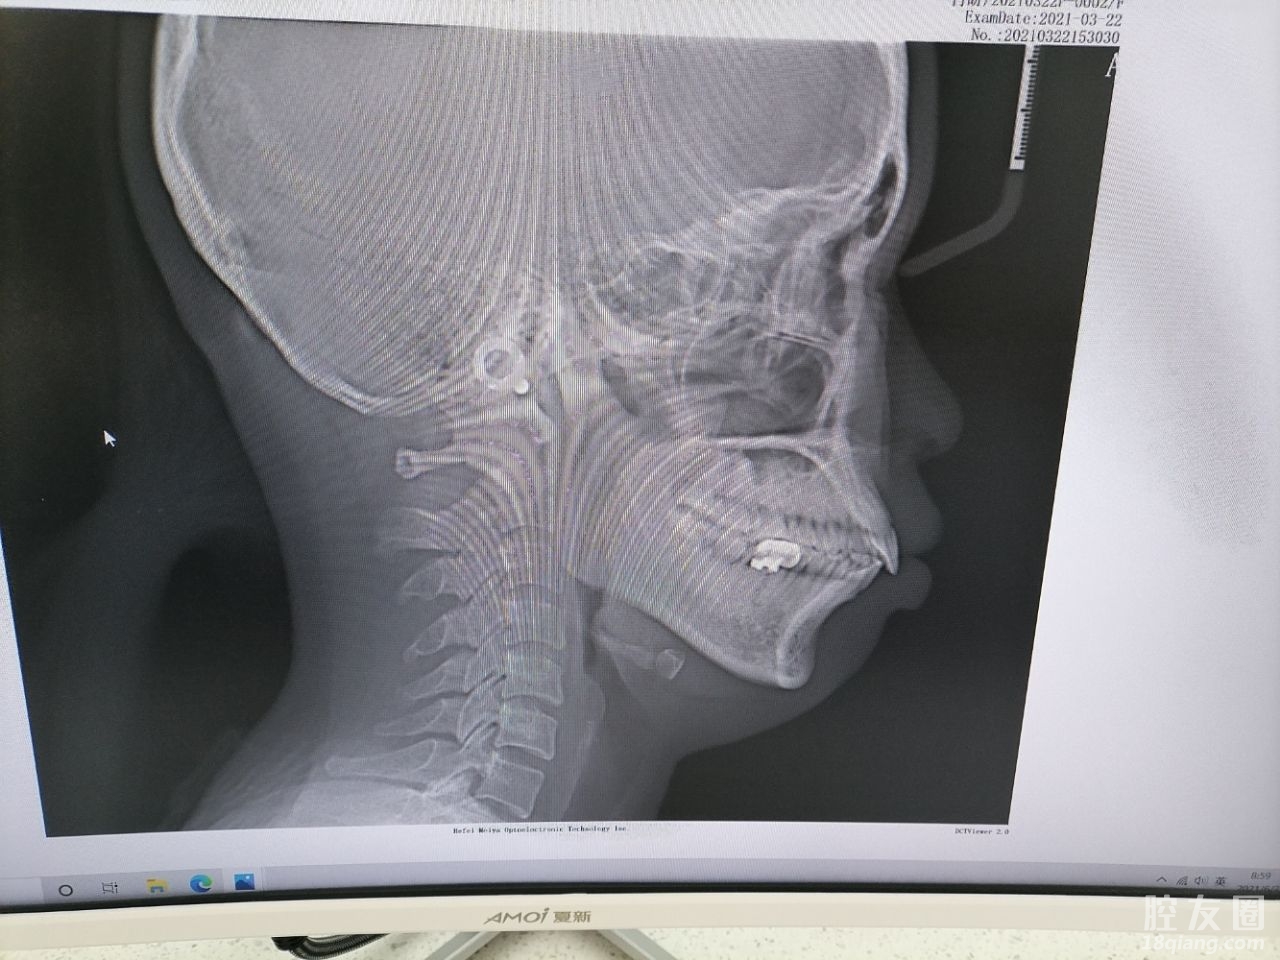

大学的时候带了钢牙套一年半了,后来因为保持器没有坚持戴,现在工作了时隔太久感觉又反复了,2021年决定彻底改变一下自己,算是给自己的礼物。

第三,技术专业,服务一流。口扫+拍片子+出方案,当天就很满意交了定金,希望矫正成功。